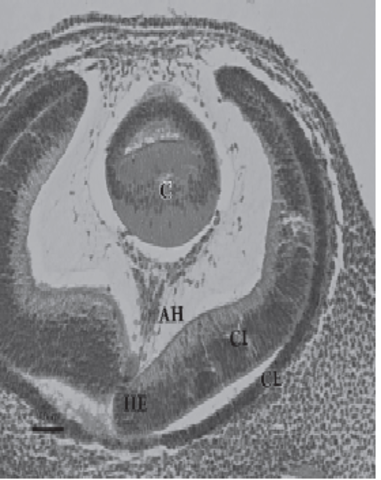

Los axones de las células ganglionares de la retina neurosensorial crecen hacia el pedículo o tallo óptico. De esta manera, la cavidad del tallo se va obliterando. La aparición de los axones en la futura papila se observa en embriones de 16 mm de longitud. Las células del pedículo óptico rodean cranealmente a estas fibras y a la arteria hialoidea

Durante el segundo mes del desarrollo comienza el cierre de la

hendidura embrionaria, debido al crecimiento de los bordes del pedículo óptico. Inicialmente se fusiona la porción intermedia y se extiende en sentido proximal y distal, hasta que a los 20 mm de longitud queda totalmente obliterada. Se observa el quiasma óptico. En la región de la futura papila aparece una acumulación de glioblastos,separando las fibras del nervio óptico del vítreo secundario

La placoda cristaliniana se invagina, hasta que un día más tarde se desprende de la superficie ectodérmica, formando la vesícula cristaliniana. Inicialmente ésta presenta una cavidad en su interior. Este fenómeno coincide con la aparición del cuerpo vítreo primario, entre la vesícula y la cúpula óptica Las fibras de la pared profunda de la vesícula cristaliniana se diferencian para formar las fibras primarias del cristalino. De esta forma, se va obliterando lacavidad de la vesícula cristaliniana